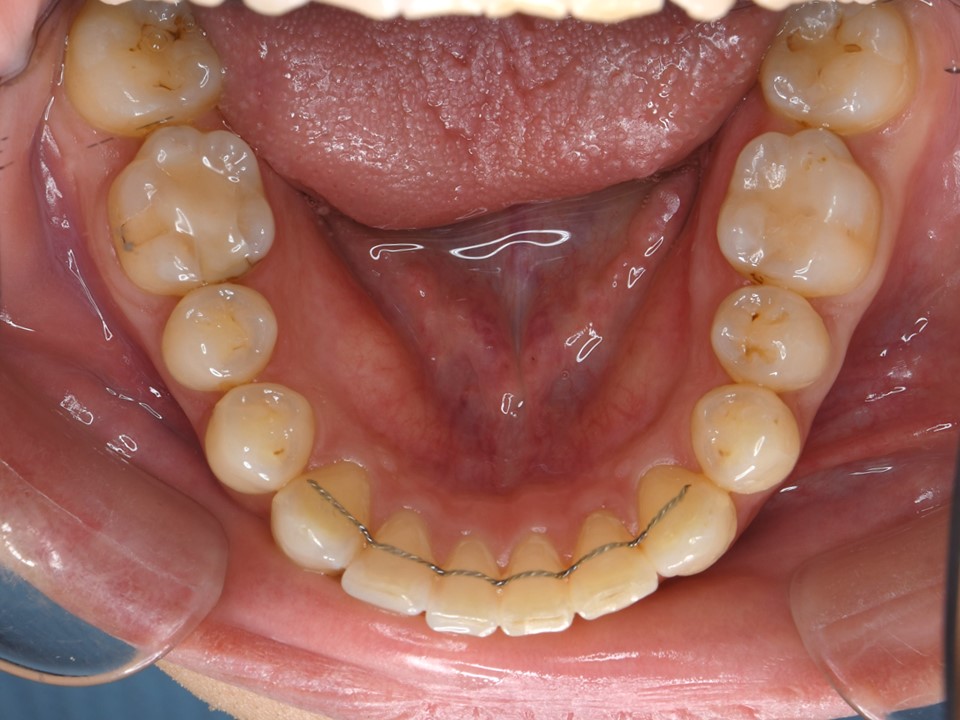

歯周病による歯列不正の矯正治療後。上下前歯部の叢生は改善し、左右対称の美しい歯列になった。欠損していた右側下顎第一大臼歯は、インプラントにて欠損補綴を行った。歯周病の矯正治療後では、歯の支持歯槽骨の減少により歯並びの後戻りを生じやすいため、厳密に長期間保定を行う必要がある。本症例ではワイヤー(FIX)にて保定を行った。